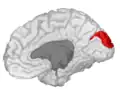

![]() Medial surface of left cerebral hemisphere. (Cuneus visible at left in red.) | |

Medial surface of left cerebral hemisphere. Cuneus is visible at left in green. -